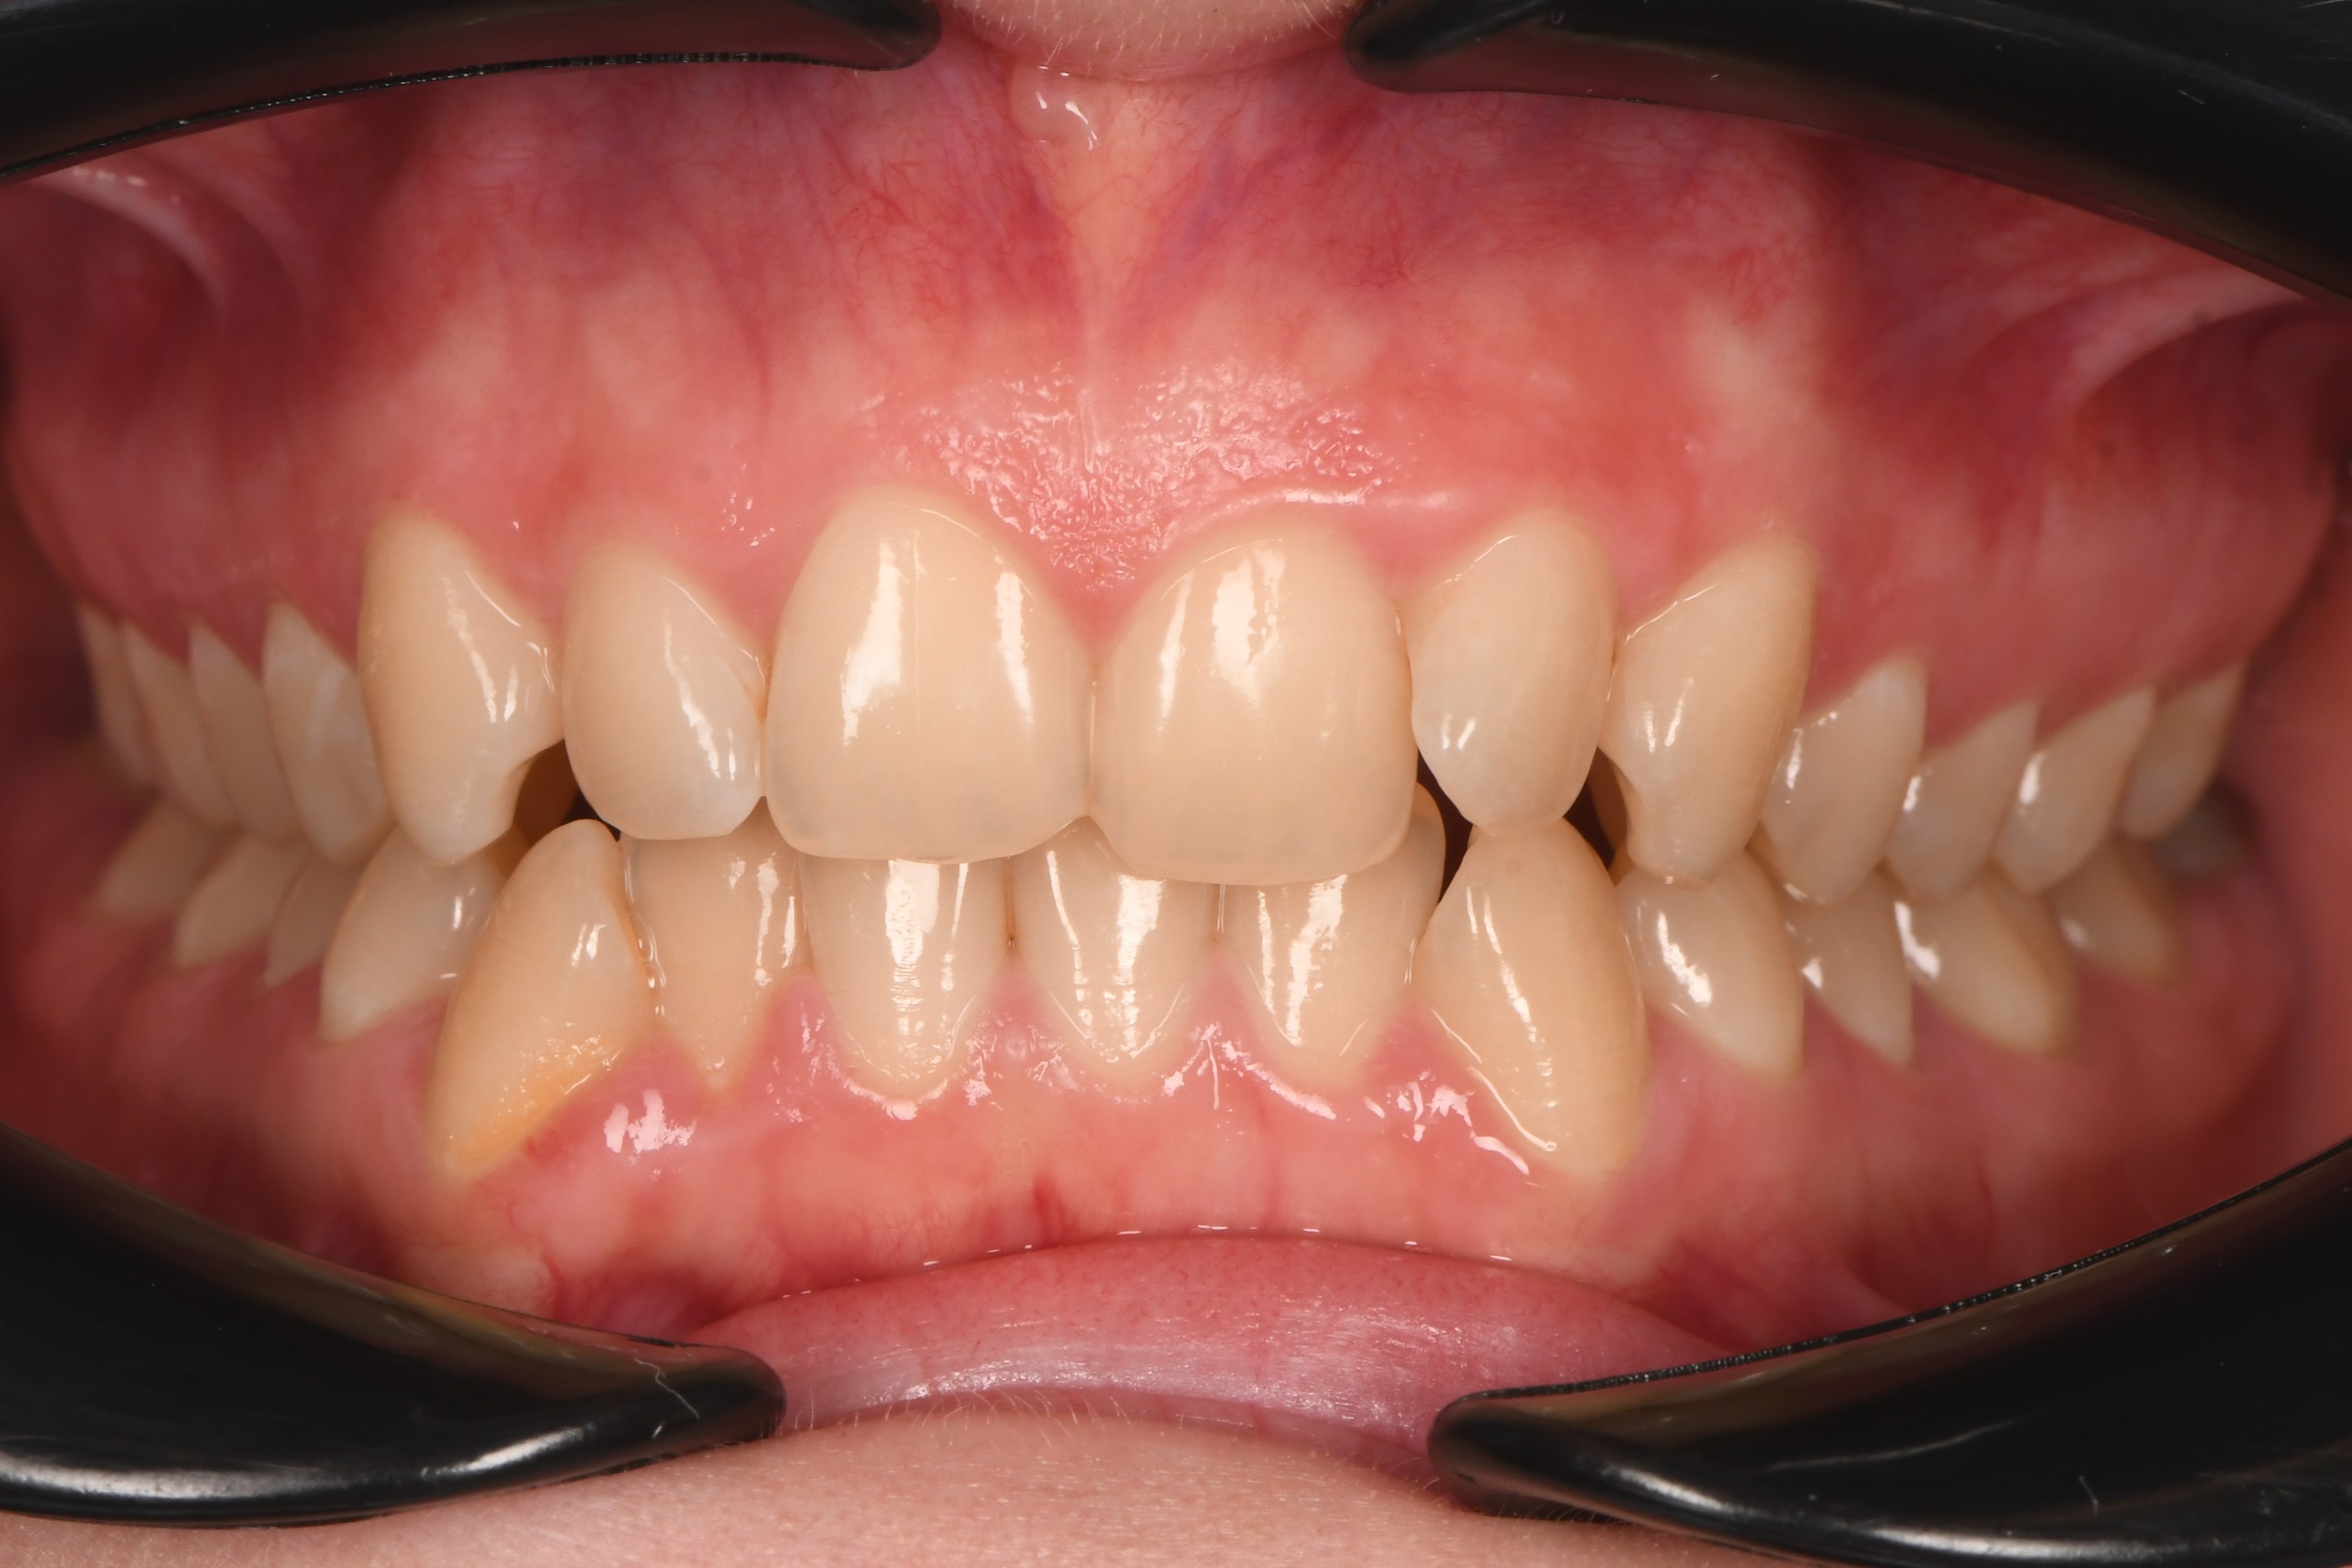

Мне хотелось идеальной улыбки. А мой нижний зуб закрывал наоборот верхний. Теперь моя улыбка - совершенна!!!

Нижние зубы впереди верхних, есть неудобства при жевании, не нравится моя улыбка и форма зубов.

Меня беспокоил один зуб, который прорезался в десне неправильно. Я решилась на ортодонтическое лечение и теперь моя улыбка добавляет мне уверенности в себе!

Меня беспокоил клык в десне и не нравилась моя улыбка. После ортодонтического лечения в клинике ОК я просто счастлив и улыбаюсь чаще! Спасибо!